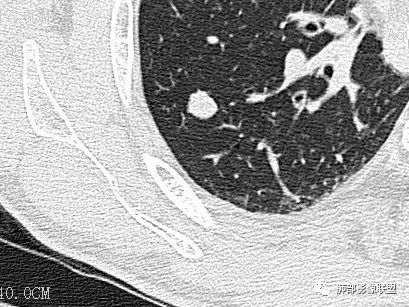

case 1

光明:

MGGO,边界清楚,胸膜凹陷,考虑LPA? 医学百科网 | YxBaike.Com

Clover: 医学百科网 | YxBaike.Com

混合GGO,收缩力弱,部分边缘似清非清,圆洞样胸膜凹陷 医学百科网 | YxBaike.Com

错过:

近胸膜处,边缘似清非清,血管进入,胸膜凹陷,结合CT值,考虑IAC

混合磨玻璃,收缩力弱,部分边缘似清非清,圆洞样胸膜凹陷,血管进入增粗,LPA,粘液腺癌?

王兆宇:CT值中央区偏高

Coke with ice:

洞壁感觉不像粘液腺的洞,不够光整,牵拉有点重。 医学百科网 | YxBaike.Com

胸膜下mggo,边界部分不清,部分清晰,胸膜凹陷,考虑粘液腺,建议抗炎后复查 医学百科网 | YxBaike.Com

王兆宇:边界很清楚啊 医学百科网 | YxBaike.Com

MIA(微浸润腺癌) 医学百科网 | YxBaike.Com

@江登科 内部的高密度区>5mm 医学百科网 | YxBaike.Com

这个层面看着挺清晰。病灶最下缘感觉不太清

是大于5mm IAC(浸润性腺癌) 胸膜还是有牵拉 医学百科网 | YxBaike.Com

这例圆洞样的胸膜,造成一定难度 医学百科网 | YxBaike.Com

圆洞的底不太光滑

牵拉洞壁不够光滑,洞底感觉坑坑洼洼的 医学百科网 | YxBaike.Com

浸润性腺癌

病理结果没有记录附壁生长的成分。我认为附壁生长为主型LPA。通常收缩力明显的,是裂隙状胸膜凹陷 但在肺尖部,可能胸膜有一定的壳样增厚,所以可以圆洞样 医学百科网 | YxBaike.Com

一句话小结: 医学百科网 | YxBaike.Com

胸膜下孤立较大混合密度结节影,中央实行密度,周围磨玻璃边界清楚提示存在小叶间隔阻挡。局部明显胸膜凹陷,提示病灶较强收缩能力,这也很少见于粘液腺癌。 医学百科网 | YxBaike.Com

综上更符合浸润性腺癌。